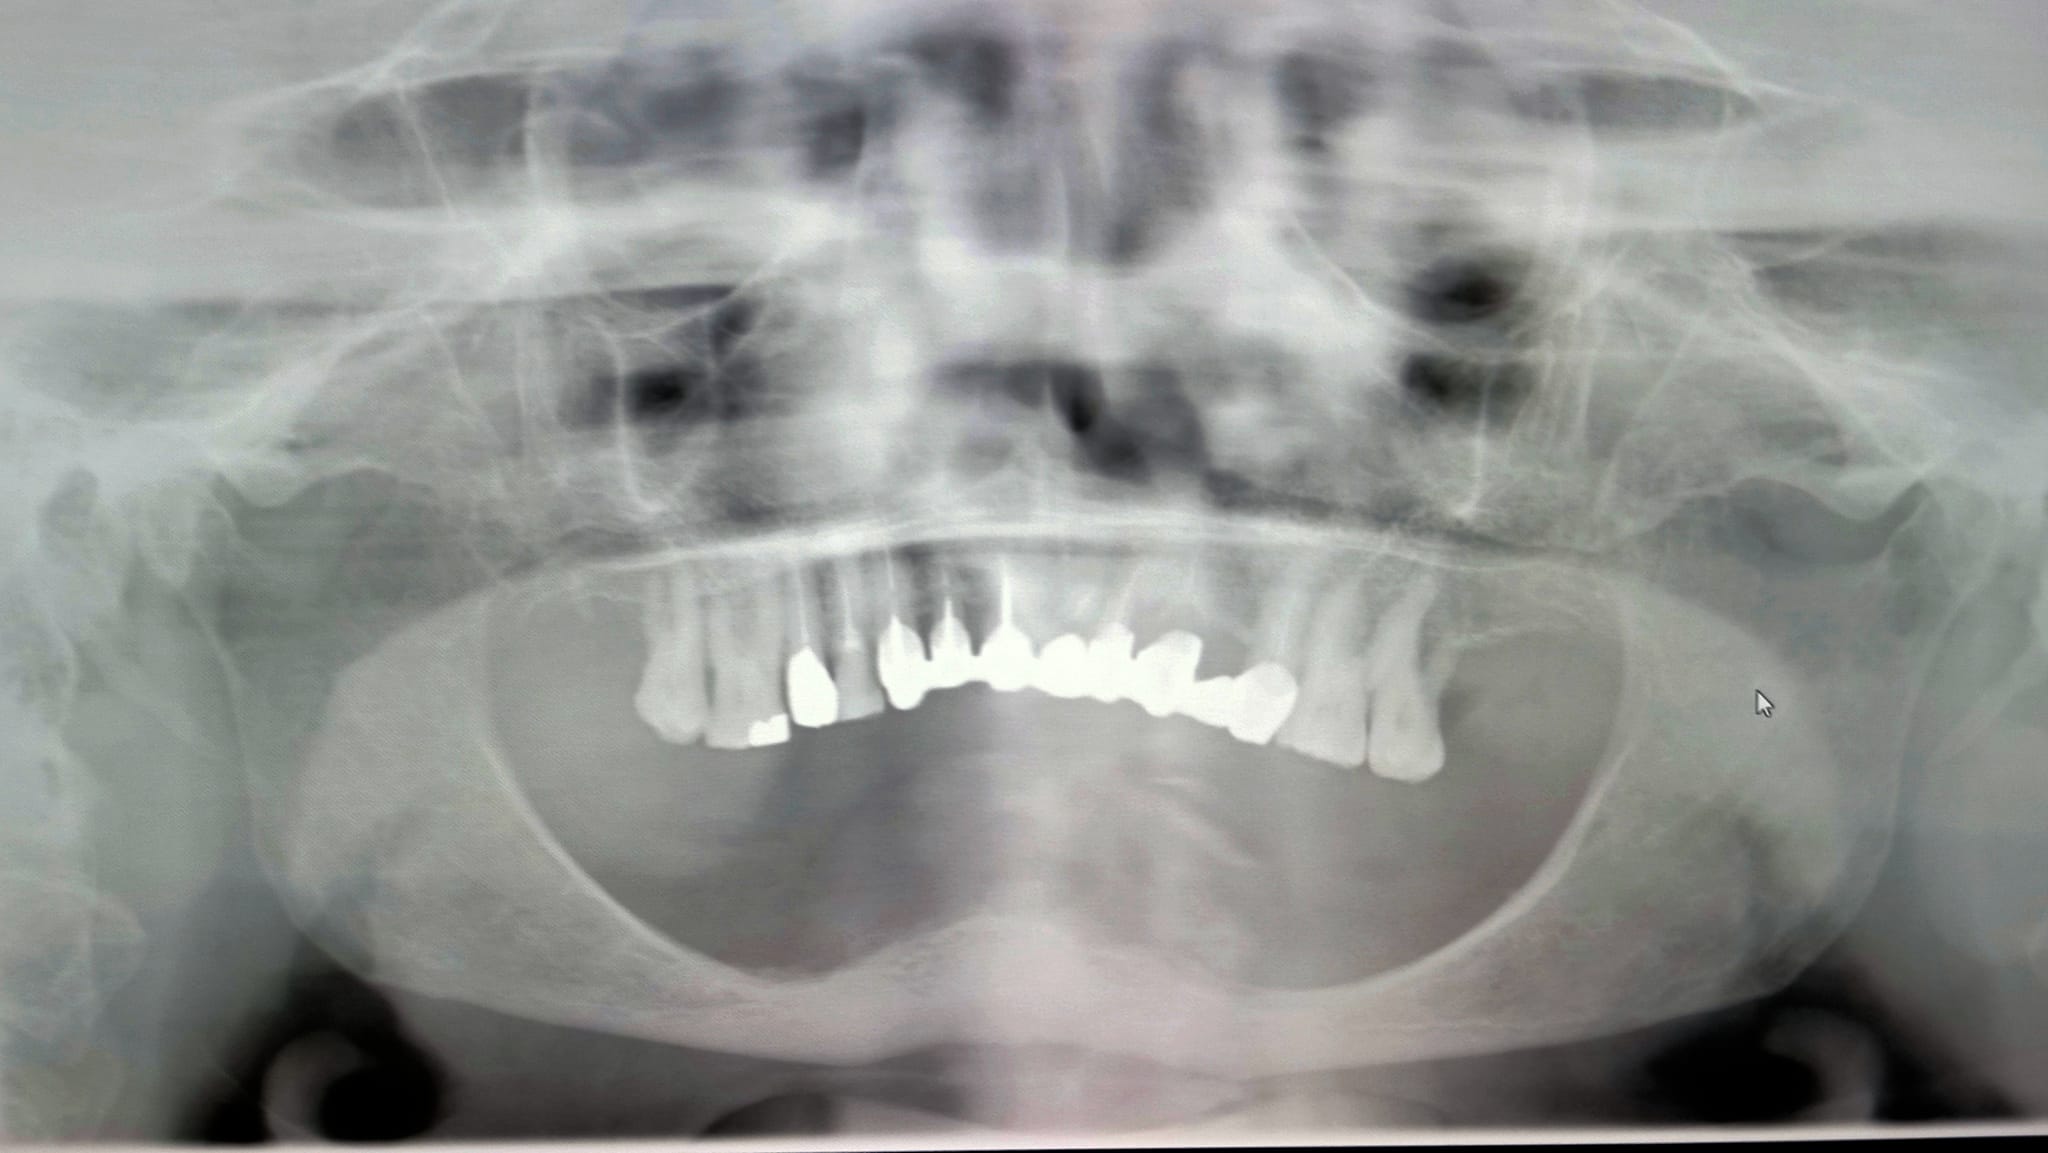

Parleremo del trattamento di questa mia paziente, trattata cinque anni fa, che mi sembra molto simile a quello del collega.

Ora che hai capito come la penso riguardo a (quasi) tutte le mandibole edentule del mondo penso sia arrivato il momento di dare un’occhiata al mio intervento di 5 anni fa che magari qualcuno potrà trovare utile… e sai una cosa? Oggi, 5 anni dopo, avrei fatto esattamente gli stessi movimenti… nello stesso ordine!